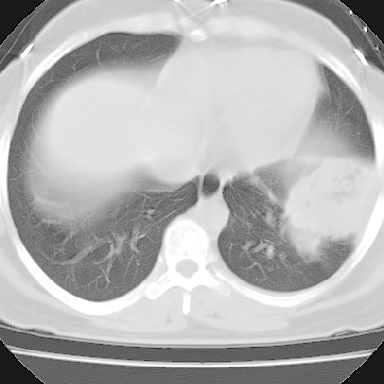

f 37 咳嗽1周,咯血1次,无浓痰,无明显发热

左下肺肿块影,内可以见小泡征,并见厚壁空洞形成,洞内缘凹凸不平,可见壁结节。靠近胸膜侧可见胸膜凹陷征。左侧胸腔内可见少量低密度积液影。右肺可见两处高致密的小结节影。

考虑:左下肺周围型肺癌伴右肺转移

左下肺肿块影,内可以见小泡征,并见厚壁空洞形成,洞内缘凹凸不平,可见壁结节。靠近胸膜侧可见胸膜凹陷征。左侧胸腔内可见少量低密度积液影。双肺可见多发性小结节影。

考虑:左下肺癌性空洞伴两肺转移

左下肺肿块影,内可以见小泡征,并见厚壁空洞形成,洞内缘可见壁结节。靠近胸膜侧可见胸膜肥厚粘连。双肺可见多发性小结节影。

考虑:左下空洞性肺癌伴两肺转移

偏心性厚壁空洞,壁结节,胸膜肥厚粘连,双肺多发性小结节灶。这么多典型征象,即使错了也错的有道理!